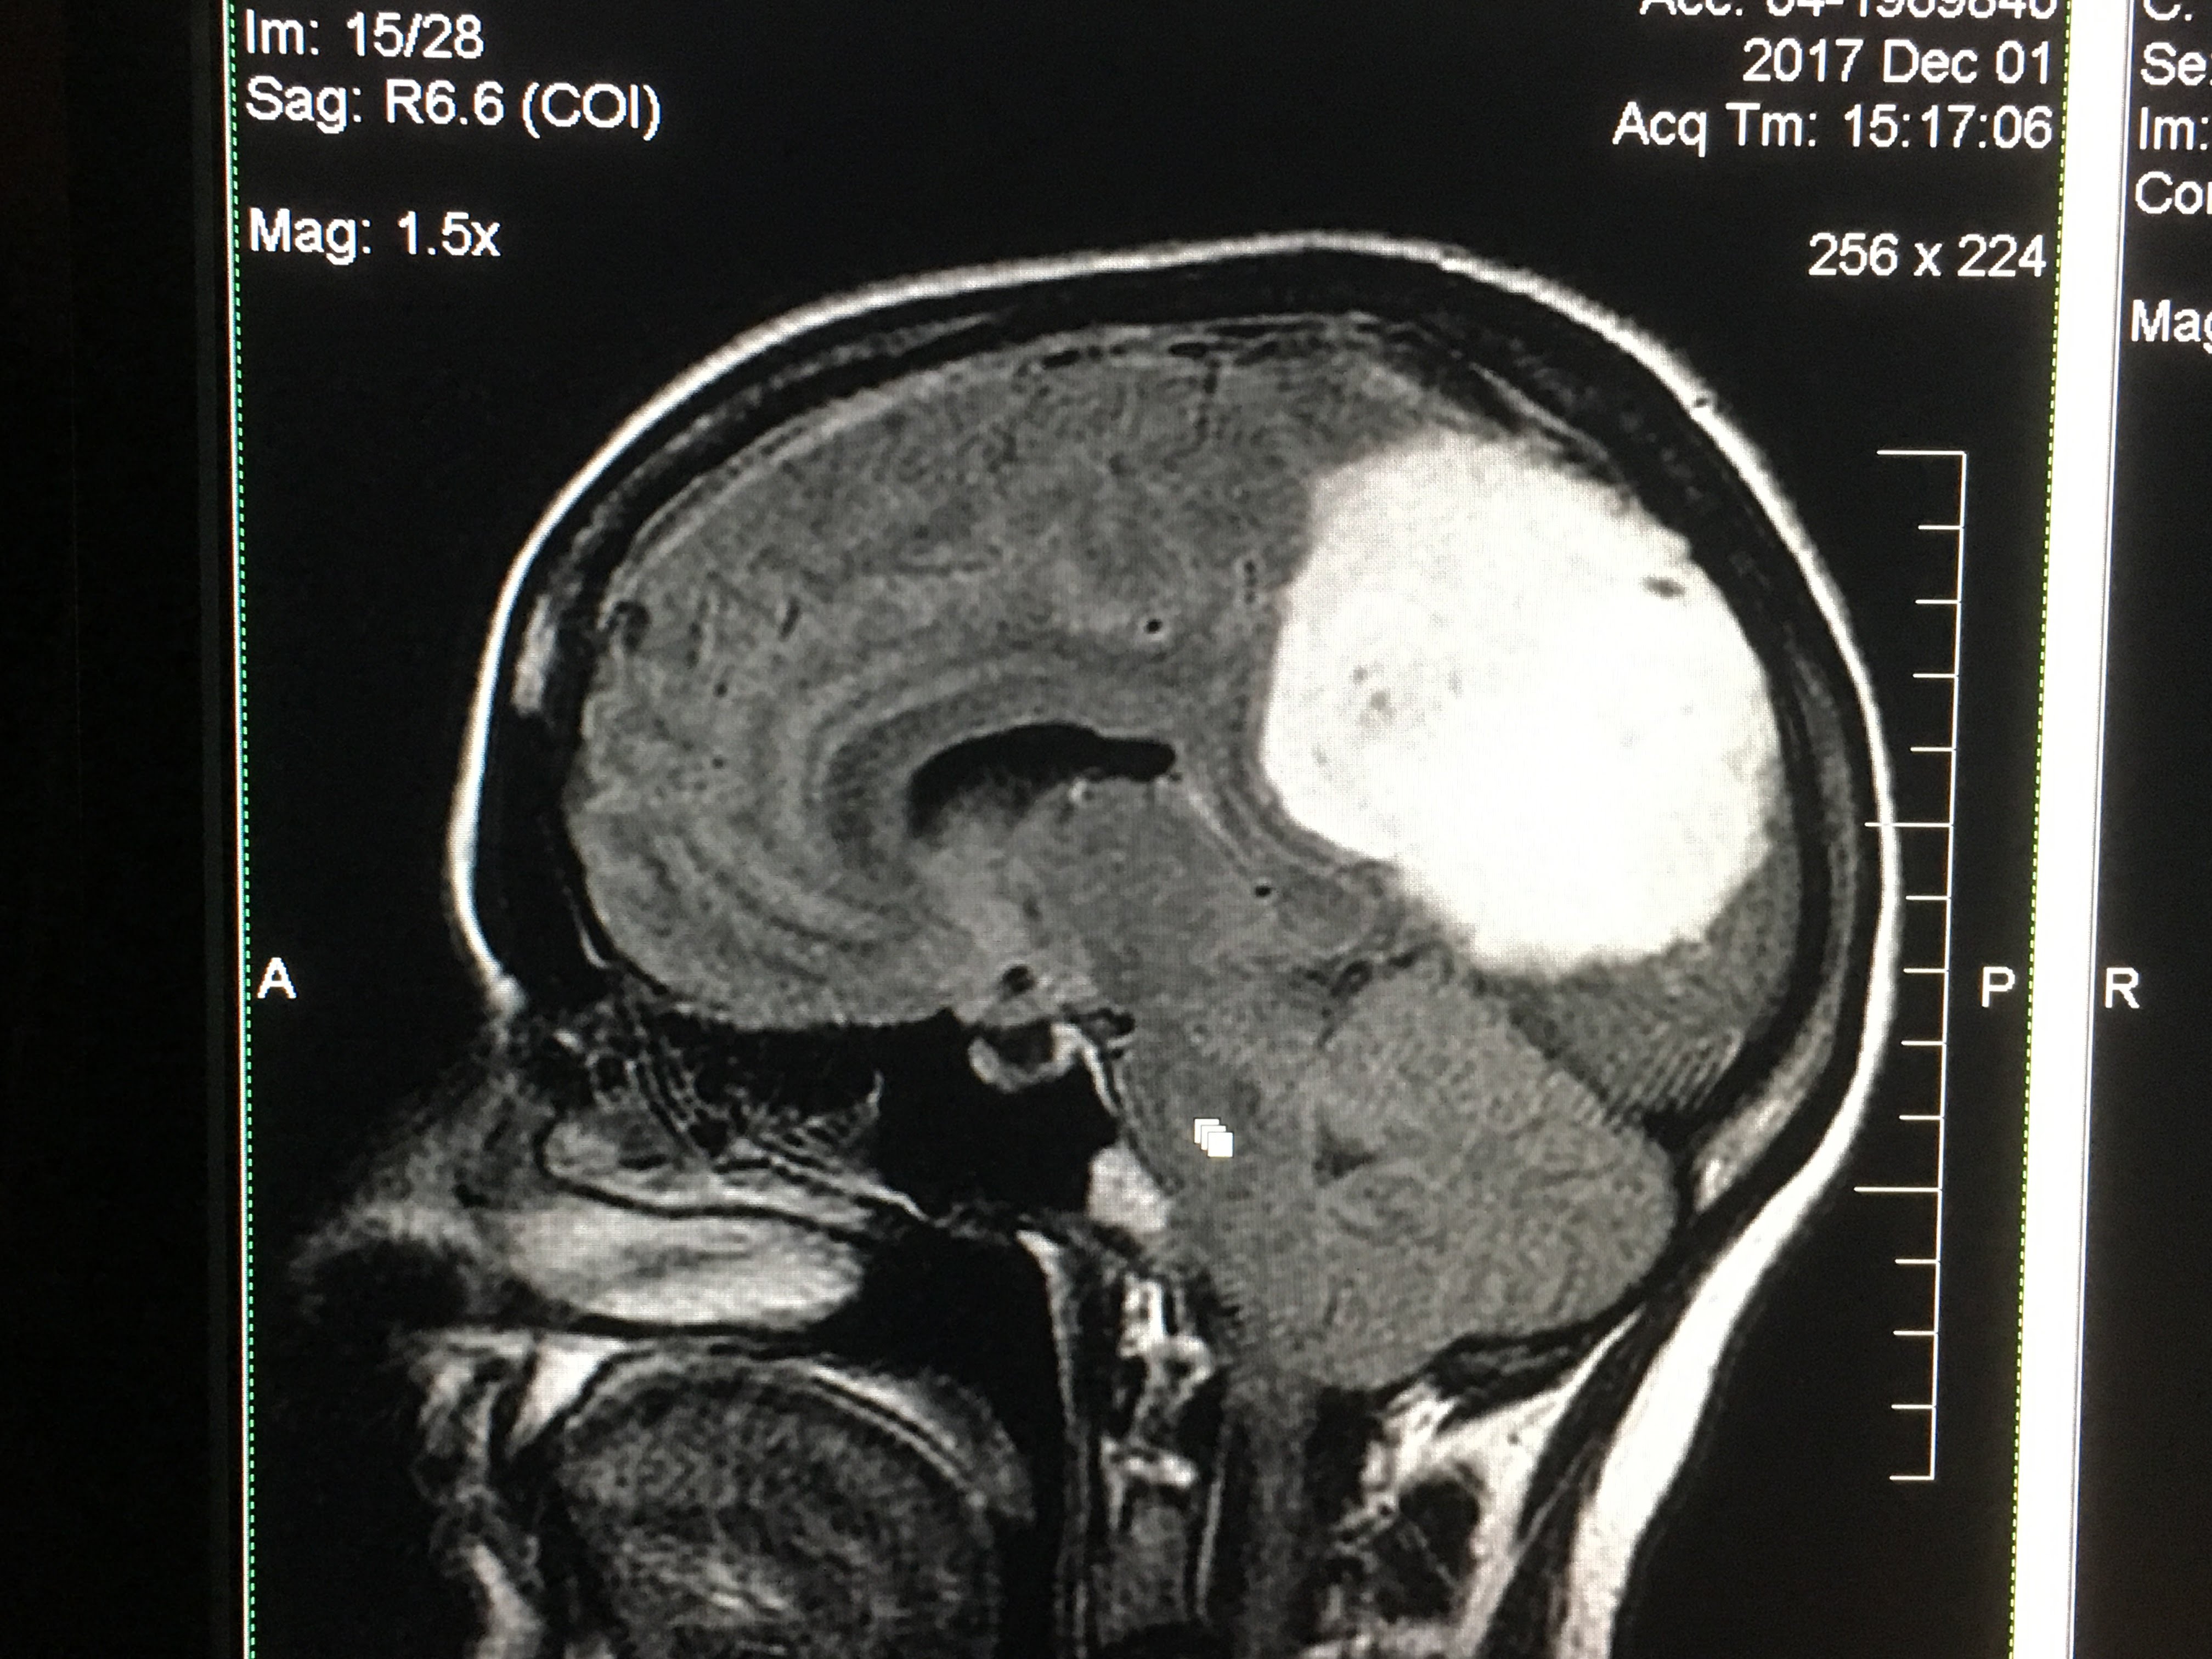

Brain trip